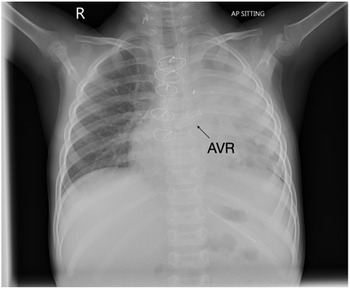

Despite escalating inotropic and mechanical ventilation support, she required placement on extracorporeal membrane oxygenation due to persistent decompensated cardiac failure despite maximal ventilatory and inotropic support. Cardiomyopathy and myocarditis work-up failed to identify an underlying aetiology. Given her need for ventricular assist device support and listing for orthotopic heart transplant, she was transferred by air ambulance to the transplant centre in Newcastle, England. Two days after arrival in the transplant centre she was placed on biventricular assist device but failed to show any recovery of ventricular function. She had a Berlin heart inserted 2 days after she was placed on biventricular assist device. She underwent orthotopic heart transplantation 3 months after transfer to transplant centre. She was initially treated with intravenous cyclosporin before transitioning to tacrolimus. Subsequently, she developed Enterococcus faecalis bacterial endocarditis resulting in severe aortic regurgitation. This was not amenable to valve repair and required aortic valve replacement (AVR) with a 19 mm On-X valve 11 days after her transplant.

This is the first reported aortic valve replacement in a child after cardiac transplantation using an On-X valve. Although attempted repair was contemplated, the valve destruction was too severe warranting replacement. Given the size of the donor heart, it was possible to implant 19 mm valve in this 12 kg child with minimal risk of patient prosthesis mismatch. Her most recent echocardiogram demonstrated excellent prosthetic valve function with mild para-valve regurgitation, mild LV dilatation, global longitudinal strain -19% and left ventricular ejection fraction 60% (Simpson’s biplane). Benefits of the On-X valve include its unique material and design characteristics compared with earlier generations of mechanical valve. The valve also can be used safely with less anticoagulation (INR 2-3 for first 3 months; INR 1.5–2 thereafter). (1). In a prospective randomized trial, patients using lower dose anticoagulation had at least 60% fewer bleeding events without any increase in their stroke risk (2). Furthermore, the valve has a much lower reoperation risk compared to bioprosthetic tissue valves. This report highlights the potential for successful outcome of AVR using the On-X valve post orthotopic heart transplant despite significant co-morbidities in this patient.

Figure 1. Chest radiograph demonstrating bileafelt On-X aortic valve.